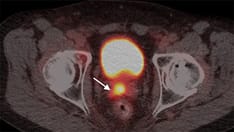

Computed tomography (CT) and/or MRI of the abdomen/pelvis are performed in a risk-stratified approach. Chest radiography is no longer a routinely advisable staging test for prostate cancer, though it may be of use in patients with prostatic ductal adenocarcinoma.

Advanced imaging utilizing multiple radiotracers is currently being evaluated for localized prostate cancer staging, but it has not yet been standardized for clinical practice and staging and is beyond the scope of this article. [96]